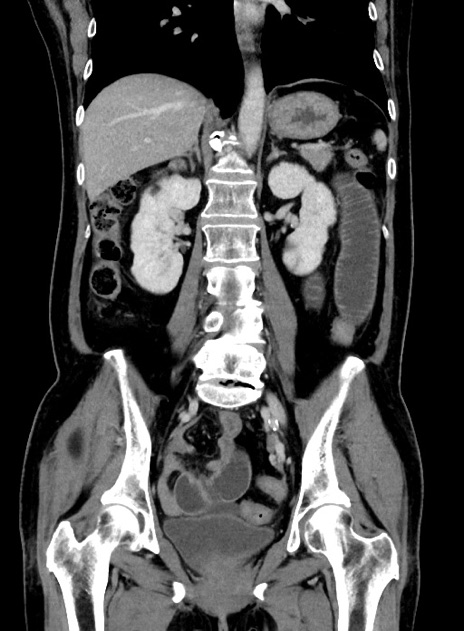

症例9(冠状断像)

【症例】 60歳代女性

【主訴】むかつき、みぞおちの痛み

【現病歴】3日前よりむかつきがあり、食事がとれない。

【既往歴】糖尿病

【身体所見】発熱なし、心窩部圧痛軽度あるも、腹膜刺激症状なし。

【データ】WBC 7400、CRP 1.92